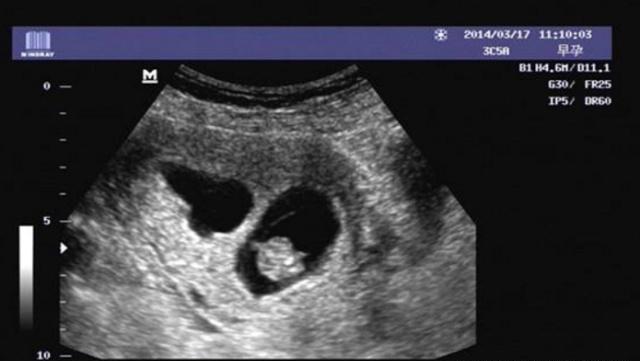

怀孕50天的孕囊,能根据B超单上的数据,看出胎宝宝的性别吗?

孕囊也叫妊娠囊、胎囊。一般情况下也能在女人子宫内的位置都是比较正常的,只有孕囊没有出现模糊不清或者是太靠后的情况就可以,如果在怀孕后,孕囊在女人子宫的下部形态有些不规则,或者是出现了阴道流血腹痛的情况,就需要及时的就医了。

怀孕早期就可以看见孕囊,一般情况下月经周期是28~30天,当女性朋友停经35天左右,通过B超检查就可以看到子宫当中的孕囊了,刚怀孕到6周左右的时候,孕囊的直径会达到两厘米左右,怀孕10周左右,孕囊可能会达到五厘米左右。通过孕囊的大小和形状,我们只能够判断女人怀孕的时间,并不能判断胎儿的性别,所以说,不要太认真了。